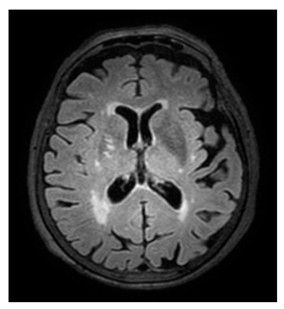

- White matter hyperintensities (WMH): Classified using the Fazekas scale (0–3) [21].

The examinations were performed using either a Philips® Achieva 3T TX (Eindhoven, The Netherlands) or a General Eletric® Signa Explorer 1.5T MRI scanner. T2-weighted sequences (Boston, MA, USA), 3D T2-weighted fluid-attenuated inversion recovery (FLAIR) or axial T2 FLAIR, diffusion-weighted (DWI), gradient echo (in some cases), and T1-weighted sequences were used. SECTRA® software (https://sectra.com/, accessed on 1 August 2024) was used to display the scans after multiplanar reconstructions.

Regarding measurements of cerebrovascular disease, there were numerous statistically significant differences between MD and controls, namely the following: higher mean Fazekas score in MD (1.1 ± 0.8 in MD vs. 0.75 ± 0.8 in controls, p = 0.013); higher EPVStotal in MD (1.20 ± 0.9 in MD vs. 0.71 ± 0.8 in controls, p = 0.001);

Higher mean SVD-3 scoring in MD (p < 0.05 irrespective of the cut-off used). Lower cutoffs for scoring WMH (Fazekas) and EPVS associated with more significant differences between MD and controls (see Table 2). Figure 2 depicts the relationship map of the SVD-3 measurement with stronger association (SVD-3 low-Fazekas + low-EPVS).